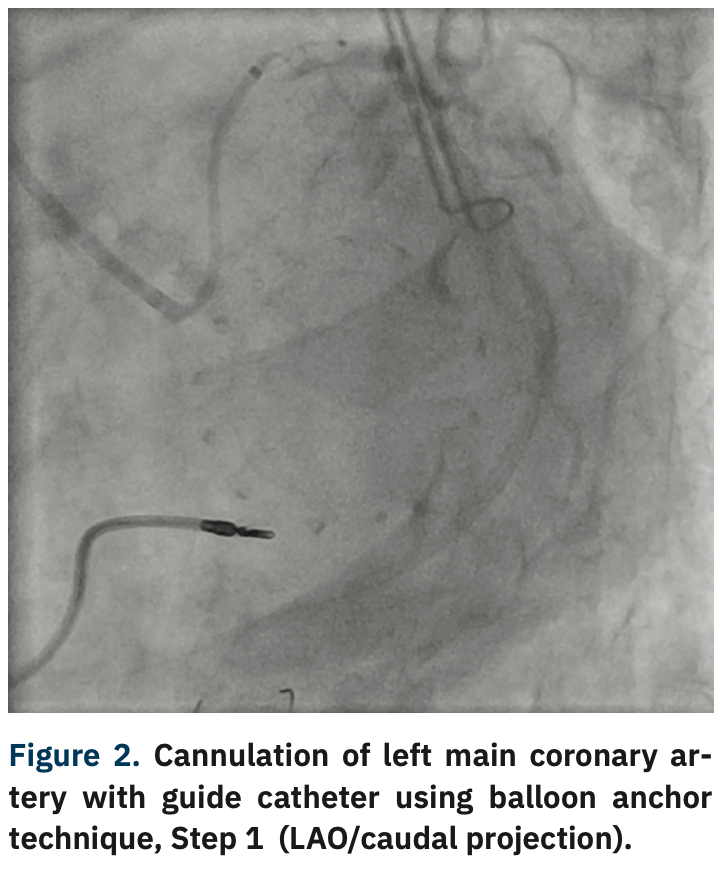

After gaining wire access to the LCx, support was increased by advancing a 5 Fr GuideLiner V3 guide extension (Teleflex) to the distal LM coronary artery. Unfortunately, even the combined support provided by the coronary guidewire and GuideLiner was not enough to allow engagement of the LM ostium with the guide. At this point, a NC Trek 2 mm x 12 mm balloon (Abbott Vascular) was advanced into the distal LM/proximal LCx and inflated to 5 atmospheres (atm) (Figure 2). With the help of this balloon anchoring, the guide catheter was gently lifted, then advanced into the ostial LM coronary artery (Figures 3-5). During this maneuver, gentle counter traction was placed on the shaft of our balloon catheter. After successful guide delivery to the LM coronary artery, the rest of the procedure was uneventful, with placement of a drug-eluting stent into the distal LM and proximal LCx with optimal angiographic result.